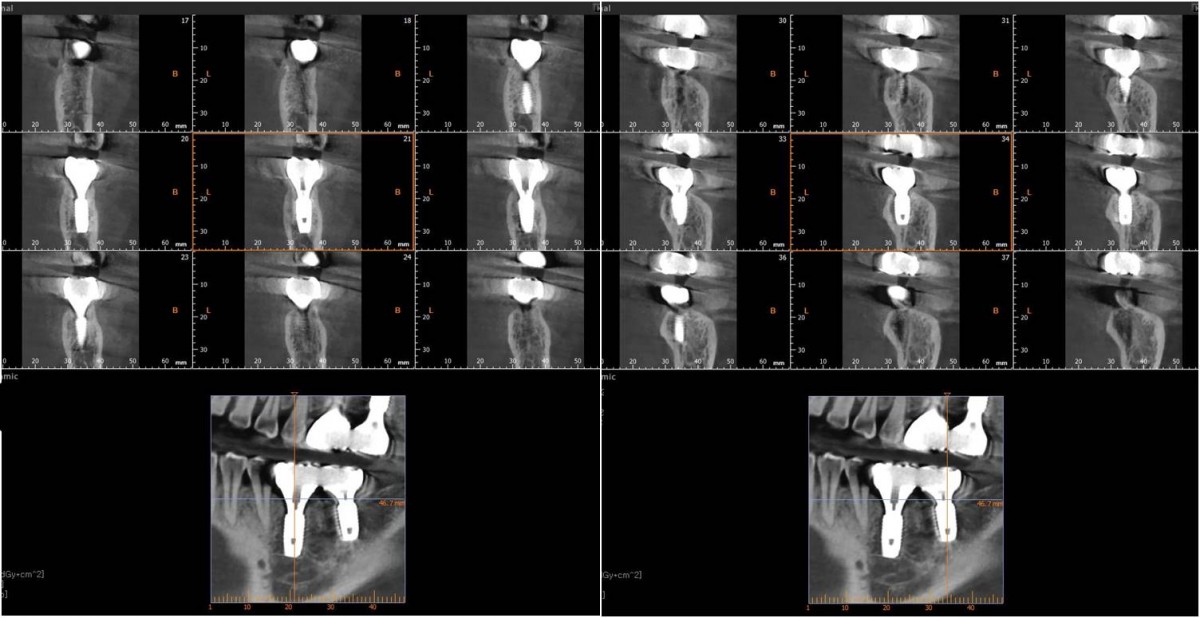

Implant in the molar zone of both jaws

A 55-year-old female patient had

bilateral problems in both jaws.

It was decided to proceed with implant-supported restoration in the left molar part first.